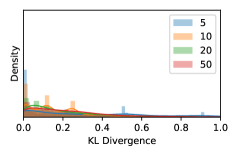

5.1 Distribution of Uncertainty Scores

Distribution of Uncertainty Scores Across Different Severity Levels As explained in Section 3, each uncertainty metric essentially defines an order/ranking among the data points. We conducted an analysis to better understand what data will be assigned high uncertainty under a particular uncertainty metric . Picking out the highest ranked data points (), we calculated the ratio of data points from each SL. Figure 4 summarizes the results as box plots for the Kaggle-DR and the Messidor-2 datasets; additional detailed statistics can be found in Table S.1 in the supplementary materials. From the plot and table, SL1 & SL2 examples account for a higher proportion among the top-ranked uncertain examples across the three ensemble methods. This finding matches our intuition that incipient disease examples (SL1 & SL2) are more likely to be considered uncertain by ensemble methods due to their ambiguity.

In contrast, the MC-dropout method showed the worst overall performance among the three, as it can be seen from the high ratios of SL0 examples among the uncertain negatives in Figure 4. The histograms in Figure 2 provides another perspective to look into the phenomenon, where a decent proportion of MC-dropout model’s predictions on SL0 inputs entailed low confidence (far from 0 or 1), which from another angle explained why MC-dropout was less specific in terms of lower FNP; many no-DR inputs (i.e. SL0) were erroneously assigned high uncertainty by MC-dropout models.

As discussed in Section 5.1 and Section 5.3 in the main paper, the mean metric and the stacking ensemble will have better performance in the precision (specificity) on the ambiguous data. Here, more detailed results are shown in Figures S.3 & S.6 and Table S.1. Figures S.3 & S.4 show the histograms of the uncertainty score for Kaggle-DR and Messidor-2 datasets that are the in-distribution (i.d.) dataset in our experiment and FigureS.5 & S.6 show the histograms for ImageNet and CIFAR-10 datasets, which is the o.o.d. datasets in our experiment. Each group of histograms contains results from the three evaluated ensemble methods (stacking ensemble, MC-dropout and TTA) and the three uncertainty metrics (mean, var and kl). Additional detailed results not displayed in Figure 4 can be found in Table S.1, which shows the proportion of the data of different SLs varies across different . For comparison, we also included in Table S.1 the results from single learners, and the proportions of data of different SLs (before any selection was made).